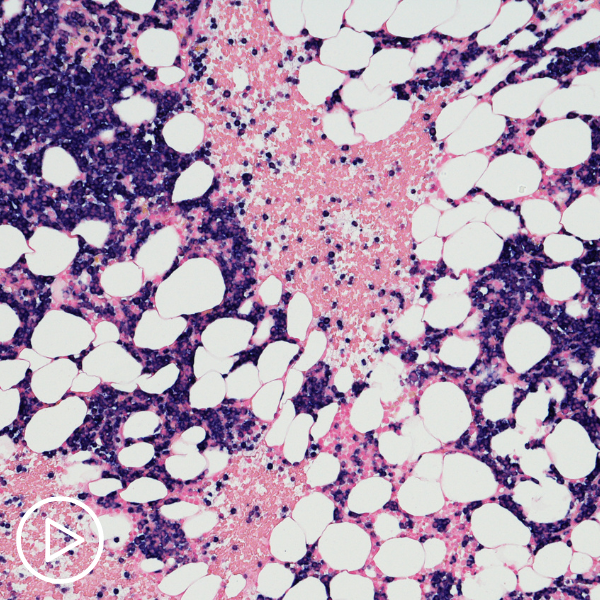

What is Multiple Myeloma (MM)?

https://vimeo.com/803667089 What happens in multiple myeloma? Watch as myeloma expert Dr. Peter Forsberg explains what occurs in the body with myeloma, and patient and Empowerment Lead Lisa Hatfield shares emotions she experienced…